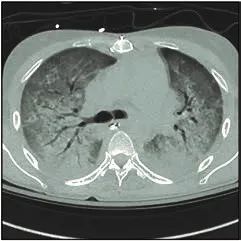

8. 静脉注射干扰素β-1a对中重度急性呼吸窘迫综合征患者死亡和无机械通气时间的影响:一项随机临床试验(JAMA 2020 Feb 17 [Epub ahead of print].)

急性呼吸窘迫综合征(ARDS)的医院死亡率为40%,除了支持性治疗,目前尚无有效药物治疗。

目前认为过度的炎症反应会导致肺血管渗漏。由于干扰素β-1a已被证明可防止血管渗漏,本临床试验旨在确定其给药是否改善了ARDS患者的预后。

中度至重度ARDS患者(n=301)随机接受10mg静脉注射重组人干扰素β-1a或安慰剂,每天1次,持续6天。主要结果是死亡和28天内无呼吸机天数的综合评分(范围:–1为死亡;如果患者在第1天即撤离呼吸机则为27)。

干扰素组死亡和无呼吸机天数的综合评分中位数为10天,而安慰剂组为8.5天(P=0.82)。与治疗有关的不良事件发生率为干扰素组41例(28.5%)和安慰剂组33例(21.7%)。

(文章选择:Martin J. London;图片: J. P. Rathmell)

关键信息:与安慰剂相比,中重度ARDS患者使用干扰素β-1a治疗6天,并未改善其预后。